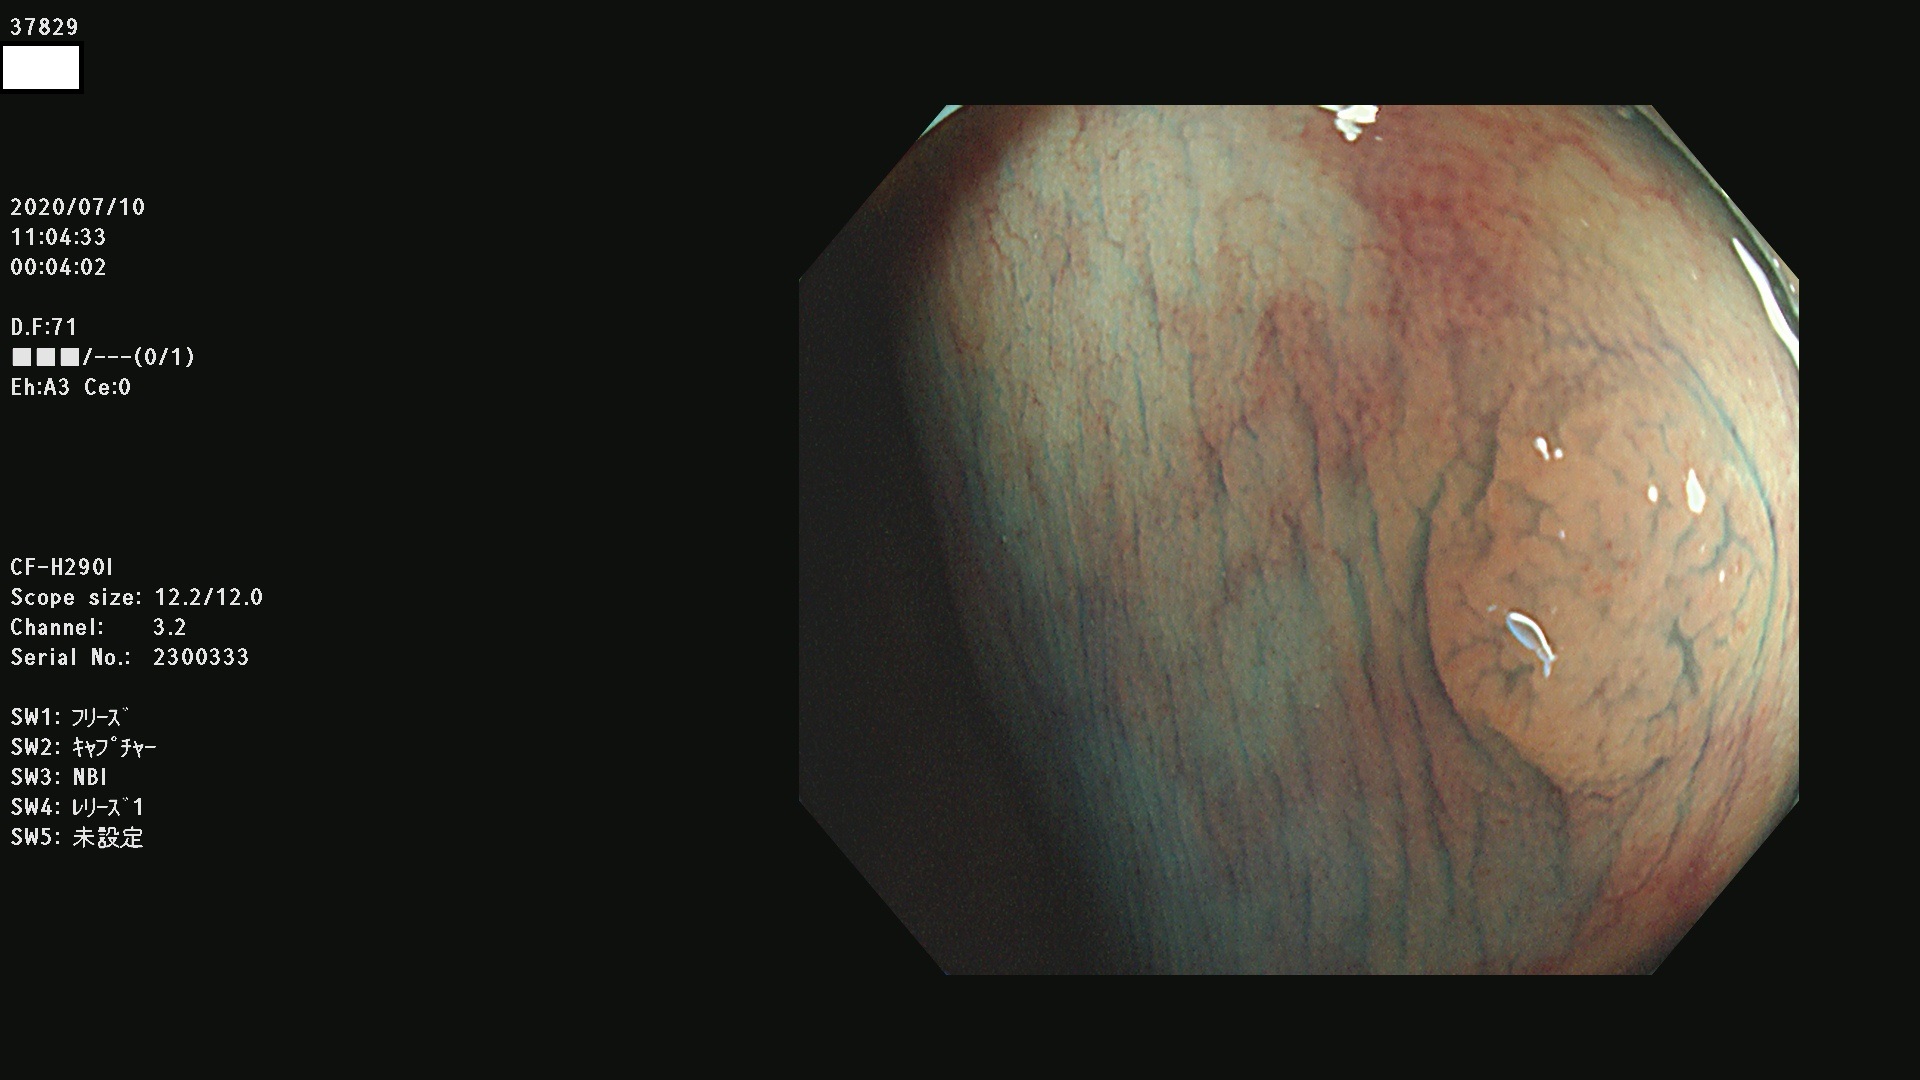

腺腫発見率 75 % (カルテ番号 37800〜37899の100名の方の検査結果で集計)大腸癌検診最新情報

以下のカルテ番号の方に腺腫(Adenoma,Group3〜5)が見つかりました(集計法)

37800(SSAPのみ) 37801 37802 37803 37804 37805 37806 37807 37808 37809(SSAPのみ) 37810 37811 37812 37813 37814 37815 37817 37818 37819 37820 37821 37822 37824 37825 37826 37827 37828 37829 37832 37833 37836 37837(SSAPのみ) 37839 37840 37842 37844 37845(SSAPのみ) 37847 37849 37850 37851 37852 37853(SSAPのみ) 37855 37856 37857 37860 37861 37862 37863 37864 37867 37868 37871 37874 37876 37877 37879 37880 37881 37882 37883 37886 37887 37888 37889 37890 37891 37892 37893 37894 37896 37897 37898 37899

発見困難で危険性の高い平坦型病変(上記100名より抽出) ![]()